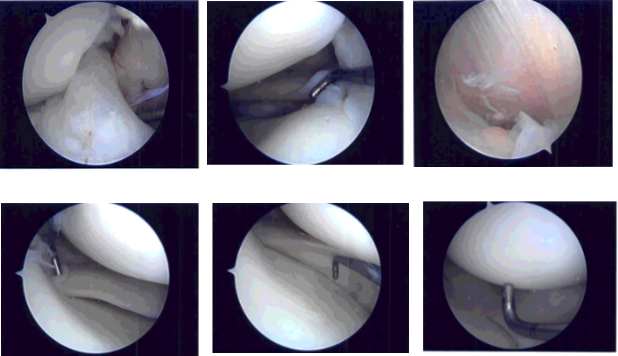

A lateral entry portal was made and the arthroscope was entered. Examination of the patellofemoral joint showed no damage. The medial gutter showed debris. The scope was moved to the medial tibiofemoral compartment where a small tear in the posterior horn of the medial meniscus could be seen.

A medical entry portal was made with the use of a spinal needle. The probe was entered and tears were confirmed. The tear was removed using upbiting and shaver. The rest of the meniscus was stable. The scope was moved into the intercondylar area where the ACL was intact.

The scope was moved to the lateral tibiofemoral compartment. There was a small tear on the posterior horn of the lateral meniscus. The tear was removed with the use of a shaver. The rest of the meniscus was intact. There was no excess movement of the meniscus.

The cartilage of the medial and lateral femoral condyle was intact. The knee scope was entered into the patellofemoral joint. Examination of the trochlea and posterior surface of circular patella was found to be intact. No arthritic changes could be found. The knee was thoroughly irrigated and drained.

Intraoperative photo

After discussing treatment options, we have decided to proceed with formal physical therapy as well as a home exercise program for rehabilitation of the knee. We went over the arthroscopic pictures and removed the stitches during today’s visit.